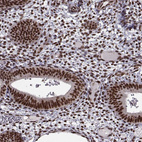

Immunohistochemical staining of human testis shows moderate to strong nuclear positivity in cells in seminiferous ducts.